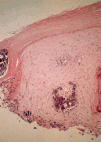

Histopatológicamente se observa material calcificado en la dermis superior en forma de masas homogéneas o agregados de glóbulos cálcicos rodeados por un infiltrado inflamatorio más bien escaso formado por macrófagos, células gigantes y mastocitos (Fig. 8). La epidermis suele ser hipertrófica y ocasionalmente puede mostrar fenómeno de eliminación transepidérmica (Fig. 9).

FIG. 8.--Depósitos de calcio en la dermis superior y reacción inflamatoria escasa en el nódulo calcificado subepidérmico.